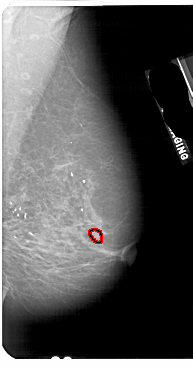

FILE: A_1737_1.RIGHT_MLO.OVERLAY

TOTAL_ABNORMALITIES 1

ABNORMALITY 1

LESION_TYPE MASS SHAPE LOBULATED MARGINS ILL_DEFINED

ASSESSMENT 4

SUBTLETY 1

PATHOLOGY BENIGN

TOTAL_OUTLINES 1

BOUNDARY